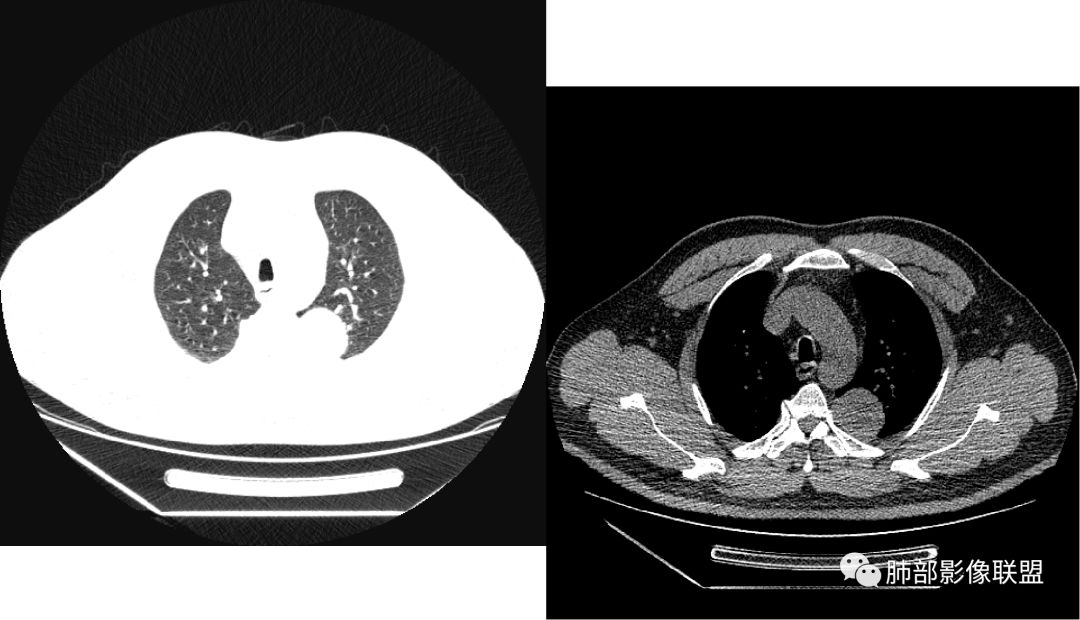

曹志勇:右肺尖后段类圆形病灶,边界清边,缘锐利,宽基底与胸膜相连,环形强化,内似见蛇纹血管征,考虑胸膜孤立性纤维瘤,右肺外底段病灶,考虑炎性可能大

红日东升:左侧胸椎旁肿块,边缘清晰光整,冠状位见D字征,未见支气管进入,肺组织受压表现,定位肺外。轻度强化,密度稍不均匀,临近肋骨变细,未见肺动脉供血,考虑良性肿瘤,神经源性可能。右肺下叶病灶,轻度强化,血管显影,边缘平直、凹陷,考虑炎性病变。

张帅:患者中年男性,咳嗽 咳痰3月,痰为白色粘痰,左上肺病灶,边缘光滑,周围未见毛刺 分叶,肺组织受挤压,与胸膜关系密切,部分层面与胸膜脂肪间隙消失,有胸膜尾征,病灶定位于胸膜,病灶增强可见强化,边缘可见增强血管,内可见低密度区,考虑 孤立胸膜纤维瘤?神经鞘瘤?右肺下叶外基底段病灶,病灶与胸膜有牵拉,病灶边缘光滑,平直 u型征,未见明显毛刺,增强病灶内可见增强血管影,边缘低密度,考虑病灶内存在痰栓。右下肺病灶考虑良性炎症性病灶,ABPA?

张立:左侧胸椎旁肿块,边缘清晰光整,冠状位见D字征,未见支气管进入,肺组织受压表现,定位肺外。轻度强化,密度稍不均匀,,未见肺动脉供血,神经源性肿瘤,节细胞神经瘤可能。右肺下叶病灶,轻度强化,血管显影,边缘平直、凹陷,TB可能。

可芸:定位:肺外病变,胸椎旁肿块,边缘清晰光整,可见胸膜尾征无支气管进入,肺组织受压。轻度强化,密度稍不均匀,未见肺动脉供血,考虑良性肿瘤,神经源性,孤立性纤维瘤?右肺下叶病灶,轻度强化,血管显影,边缘平直、凹陷,炎性病变。

薏米:左下近脊柱旁可见一结节状密度增高影,肺外,边界清,边缘规整,无分叶,无毛刺,无棘突,宽基底与胸膜相连,不均匀轻度强化,考虑为良性病变,神经源性可能性大,为神经鞘瘤,鉴别孤立性神经纤维瘤,神经节瘤,右肺片装密度增高影,考虑为炎症可能性大

崇军:左侧胸椎旁肿块,边缘清晰光整,有胸膜尾征,冠状位为D字征,定位肺外。轻度强化,密度稍不均匀,似乎看到肋间动脉供血,未见肺动脉供血,考虑良性肿瘤,神经源性可能。右肺下叶病灶,轻度强化,血管显影,边缘平直、凹陷,层面太少,暂时考虑炎性病变。

长沟流月去无声:中年男性,慢咳起病,左后纵隔可见一大占位,D字征,胸膜掀起,有胸膜尾征,附近肺组织受挤压,血管纹理纠集,瘤肺界面清晰,较均匀轻-中度强化,瘤肺表面可见线样不张之强化影,供血血管来源不易确定,冠状位似乎见一纵隔血管出入,综合考虑神经源性肿瘤:神经纤维瘤,神经鞘瘤?右下外斑片密度影,估计炎性,但本次手术应该未处理。

右叶下叶病变,顺支气管走形成不规则片样,考虑炎性

Shelia??:左下胸腔脊柱旁类圆形软组织肿块影,呈D字证,可见胸膜掀起,邻近肺组织受压呈弧形致密影改变,增强后似轻度均匀强化,邻近骨质未见明显异常,考虑良性病变,孤立性纤维瘤?鉴别神经源性肿瘤另外右肺小叶不规则病灶,边缘平直收缩为主,局部可见弓形凹陷,密度均匀,增强后轻中度均匀强化,周围肺野尚清晰,考虑炎性肉芽肿病变,OP?但是感觉周围太光整,还是就是慢性炎症?

田园晚风:左胸后部近胸椎占位,密度均匀,边缘光滑,呈d字征,外侧可见压缩肺组织,右肺见条状致密影,与支气管走行一致,考虑左侧神经源性肿瘤,右肺abpa?

张小兵:老年男性,慢性病程,咳嗽咳痰3月,左下肺脊椎旁沟区见宽基底类圆形软组织肿块,无分叶,瘤肺境界光整,其内见点状钙化,周边肺组织挤压,胸膜尾征,延迟强化,提示内含纤维成分,考虑神经源性肿瘤,SFT可能。右下肺病灶收缩力强,内见扩张支气管,提示慢性炎症,考虑机化。

1.左上胸内脊柱旁半圆形肿块,质地坚实,密度比较均匀。

2.病灶周边见胸膜掀起,应当考虑胸壁或是纵隔来源,肺内病变不会如此。

综上,病灶定位胸壁或后纵隔,就发病率而言,神经源性可能性较大。